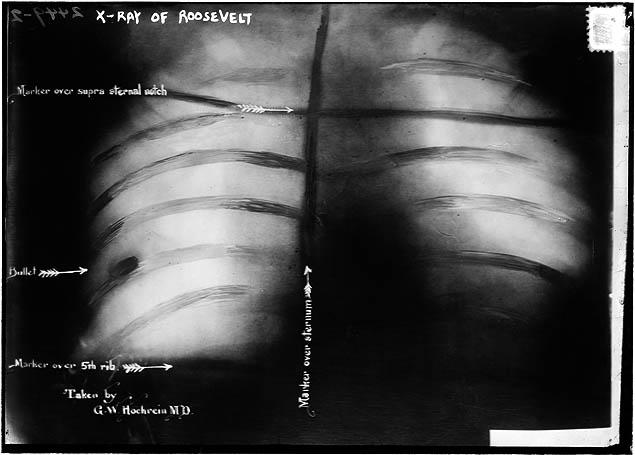

He drifted up and down the east coast for several years. In September 1912, he became obsessed with Theodore Roosevelt. For three weeks, John Schrank followed the Roosevelt campaign, stalking the candidate across eight states. On the afternoon of October 14, Roosevelt was in Milwaukee, dining with local dignitaries at the Hotel Gilpatrick, before a planned speech at the Milwaukee Auditorium. As the former President was getting into his vehicle, he turned to wave to well-wishers. Schrank was four or five feet away when he fired his .38 caliber revolver, hitting the former President in the chest.

The bullet pierced the fifty folded pages of Roosevelt’s speech and a metal spectacle case, before lodging in his chest. The former President coughed once into his hand, to see if there was blood. Seeing none, TR concluded that his lungs were fine, and decided to give the speech. The 9000+-member audience was stunned when the candidate announced “I don’t know whether you fully understand that I have just been shot—but it takes more than that to kill a Bull Moose!” Roosevelt spoke for 80 minutes, before going to a Milwaukee hospital for treatment.

Theodore Roosevelt lived the rest of his life with that bullet in his chest. Six more years. As for John Schrank, he claimed in a letter found on his person, that the ghost of William McKinley had instructed him to avenge his death with the assassination of his former Vice President. He would live out the rest of his days at the Central State Mental Hospital for the criminally insane, in Waupun, Wisconsin.